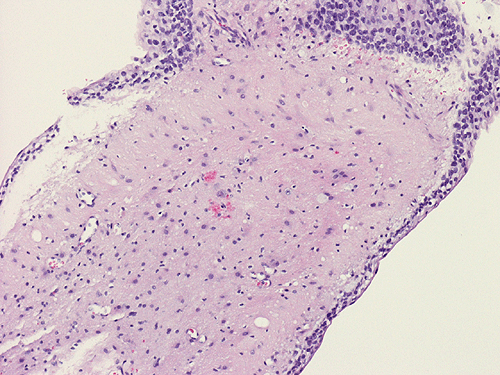

The patient was a 5 year-old Vietnamese boy who presented with the chief complaints of headaches, vomiting, and ataxia.  CT scan revealed a pineal tumor with small calcifications and hydrocephalus (Panel 1).  On MRI, the mass is a well demarcated midline mass involving the pineal area. There is also heterogeneous enhancement and cystic component (Panel 2 and 3).

The excised specimen consists of multiple fragments of tan, soft tissue, 5.0 x 2.0 x 1.0 cm in aggregate, for examination. On gross examination, neither calcified tissue nor hair were found. An intraoperative frozen section and cytologic preparation was performed which revealed mature intestinal element, skin and small amount of hair. No germinoma element, yolk sac tumor (endodermal sinus tumor) element, embryonal cell carcinoma, or immature teratoma component was present in multiple specimens submitted for frozen section. Although a minute amount of hair was revealed on the frozen section, gross examination of the submitted tissue does not identify any hair or calcified tissue. An intraoperative diagnosis of teratoma with only mature element present was made.

The entire specimen was submitted for histologic examination. The bulk (over 99%) of the tumor was composed predominantly of mature intestinal elements (Panel A, B, and C) and skin, respiratory type mucosa, cartilage, and small amount of mature neural parenchymal tissue of the central nervous system (Panel D and E). Neither immature nor malignant elements are present. Small microscopic foci of well demarcated, neural parenchymal tissue with increased atypia (arrow in panel F) are noted. On higher magnification (Panel G and H), these areas contain large, bizarre appearing cells with dark chromatin but no prominent nucleoli. There are also scant multinucleated cells and mineralized substances (arrow in Panel H). Another example of these foci is illustrated in Panel I, J, and K. These atypical foci comprised less than 1% of the volume of the tumor. They are all microscopic in size and show no evidence of expansion or invasion into the surrounding tissue.